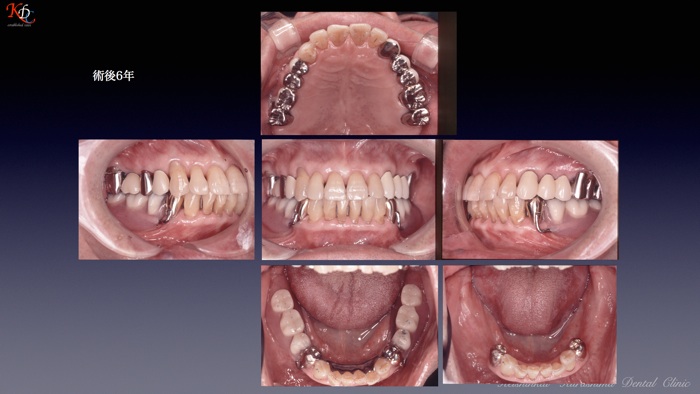

治 療例 1